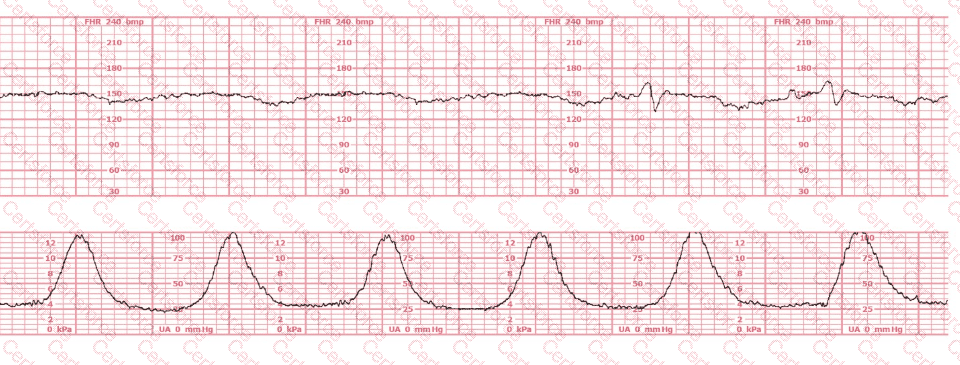

Questions # 5:

This patient received an epidural 15 minutes prior to the tracing shown. The next course of action is to:

Question # 5

A.

Check maternal blood pressure

Continue to monitor

Perform a cervical exam